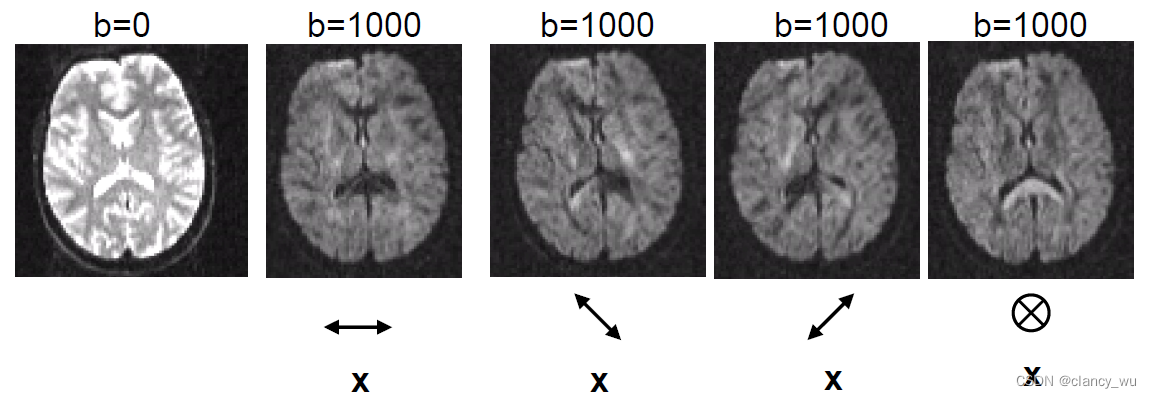

另一个就是方向: